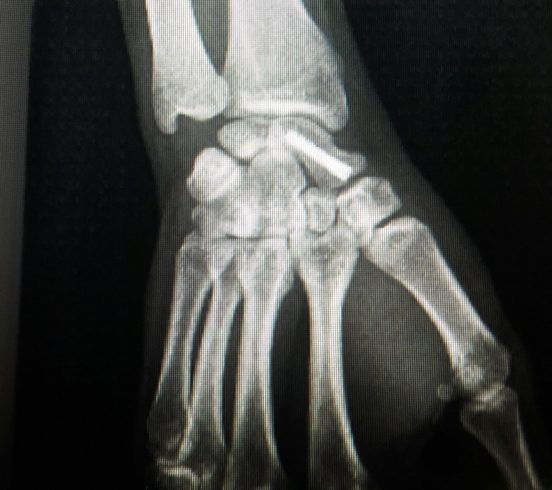

Unión de la fractura con un tornillo. Visión AP